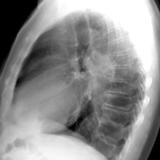

RLL collapse 4 Lat

Date: 03/02/2006

Views: 3234